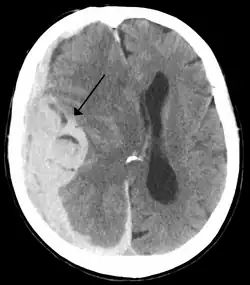

Midline shift is a shift of the brain past its center line.[1] The sign may be evident on neuroimaging such as CT scanning.[1] The sign is considered ominous because it is commonly associated with a distortion of the brain stem that can cause serious dysfunction evidenced by abnormal posturing and failure of the pupils to constrict in response to light.[1] Midline shift is often associated with high intracranial pressure (ICP), which can be deadly.[1] In fact, midline shift is a measure of ICP; presence of the former is an indication of the latter.[2] Presence of midline shift is an indication for neurosurgeons to take measures to monitor and control ICP.[1] Immediate surgery may be indicated when there is a midline shift of over 5 mm.[3][4] The sign can be caused by conditions including traumatic brain injury,[1] stroke, hematoma, or birth deformity that leads to a raised intracranial pressure.

Midline shift measurements and imaging has multiple applications. The severity of brain damage is determined by the magnitude of the change in symmetry. Another use is secondary screening to determine deviations in brain trauma at different times after a traumatic injury as well as initial shifts immediately after.[3] The severity of shift is directly proportional to the likeliness of surgery having to be performed. The degree of MLS can also be used to diagnose the pathology that caused it. The MLS measurement can be used to successfully distinguish between a variety of intracranial conditions including acute subdural hematoma,[5][7] malignant middle cerebral artery infarction,[3] epidural hematoma, subarachnoid hemorrhage, chronic subdural hematoma, infarction, intraventrical hemorrhage, a combination of these symptoms, or the absence of pertinent damage altogether.[7]